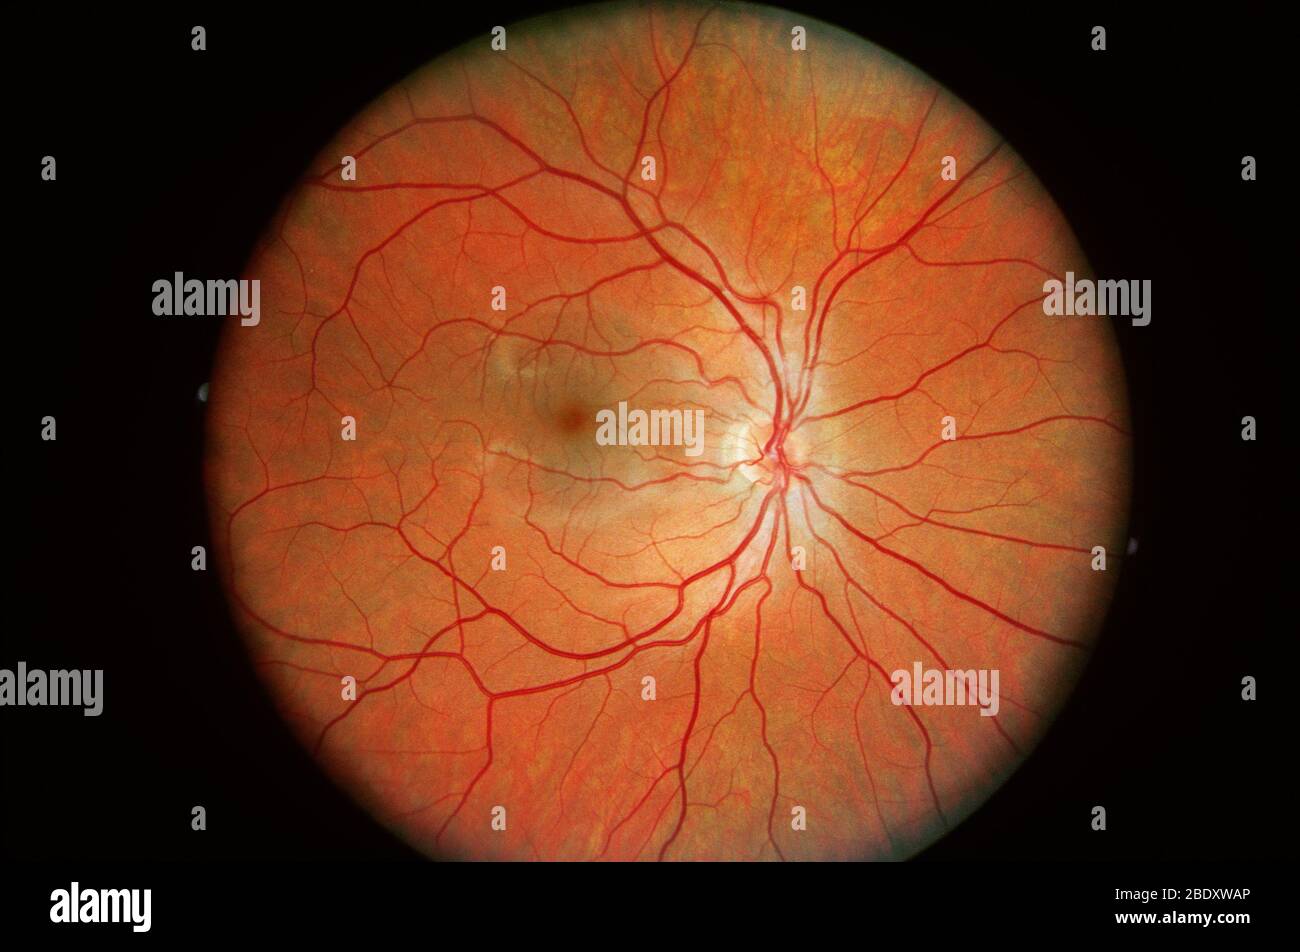

Normal Retina Stock Photohttps://www.alamy.com/image-license-details/?v=1https://www.alamy.com/normal-retina-image352788542.html

Normal Retina Stock Photohttps://www.alamy.com/image-license-details/?v=1https://www.alamy.com/normal-retina-image352788542.htmlRM2BDXWAP–Normal Retina